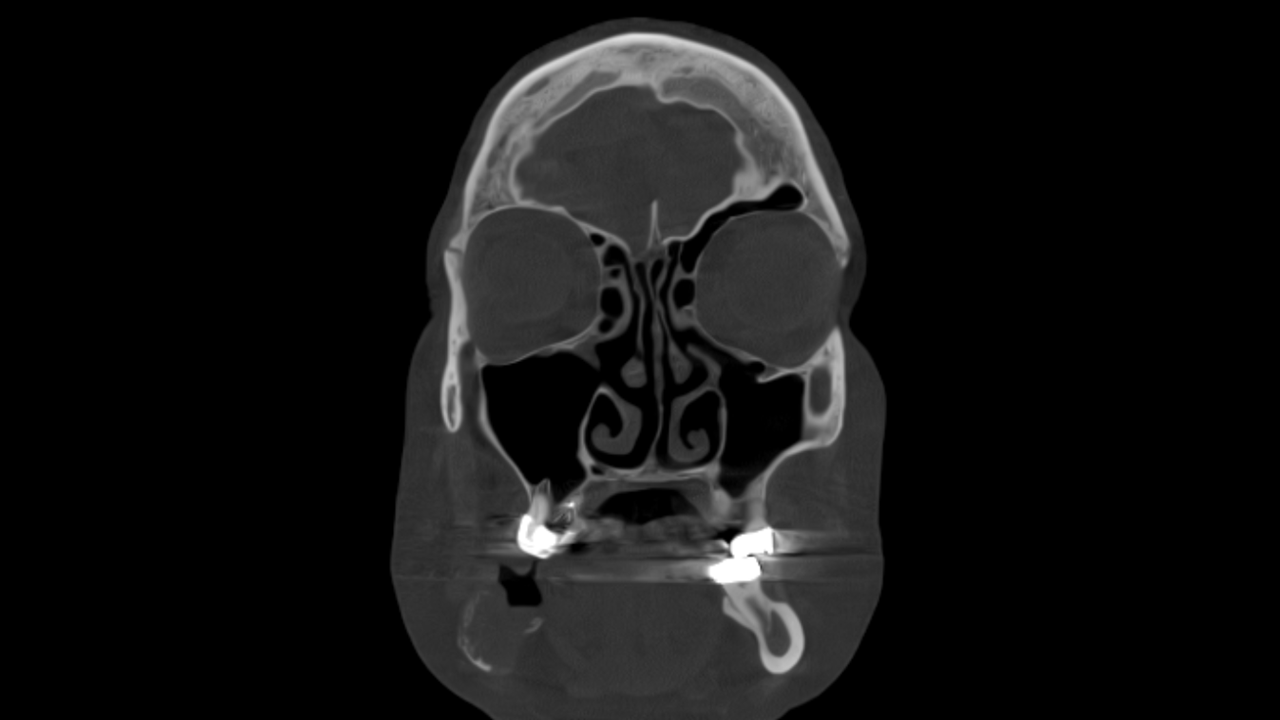

Study 3

Finding: There is an osteolytic lesion involving the right mandibular arch, characterized by effacement and expansion of the buccal and lingual cortices. Notably, there is destruction of the alveolar crest, and the cortical boundaries of the mandibular canal are eroded. These imaging findings are highly suggestive of a malignant lesion.